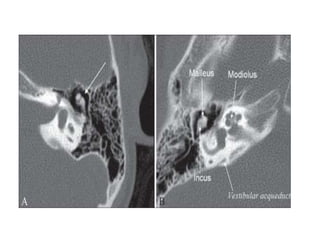

High Resolution Axial Ct Image Demonstrating The Ice Cream Sign Of The Download Scientific Diagram

High Resolution Axial Ct Image Demonstrating The Ice Cream Sign Of The Download Scientific Diagram from www.researchgate.net